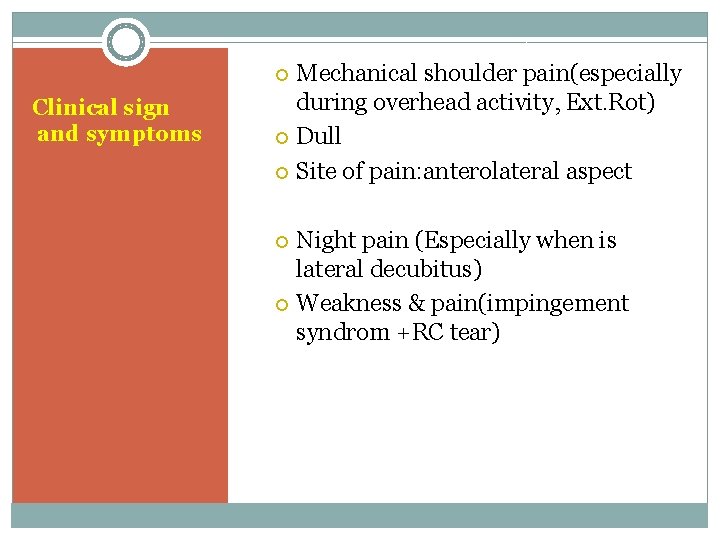

Mechanical shoulder pain(especially during overhead activity, Ext. Rot) Dull Site of pain: anterolateral aspect Clinical sign and symptoms Night pain (Especially when is lateral decubitus) Weakness & pain(impingement syndrom +RC tear)